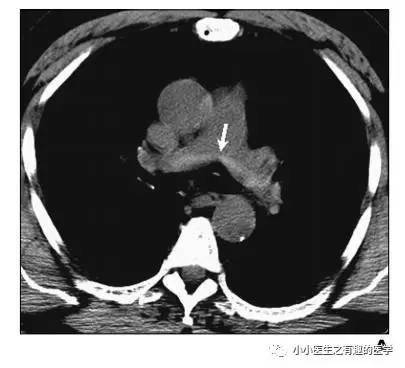

病例介绍二:

作者单位:Department of Radiology, University of Washington MedicalCenter, University of Washington School of Medicine。华盛顿医科大学。

翠花上菜,学者上图。

发现嫌疑犯,立即逮捕。

增强CT对比,一目了然。

上面的病人,增强CT放大了。

下面是另外一个:

星号的地方。